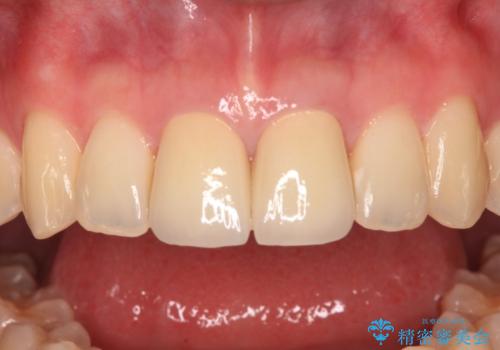

変色した前歯 オールセラミッククラウンにより審美歯科治療

- 神経を取り除いたことで経年変色した前歯2本を気にして来院された患者様です。

根管治療を行う必要はないと判断し、双方の歯にグラスファイバーを含有した土台を植立してオールセラミッククラウンにて補綴することとしました。

色調が周囲の歯とアウトともに、表面のつぎはぎや穴を封鎖した際の段差などが解消され、天然歯のような感触となりました。